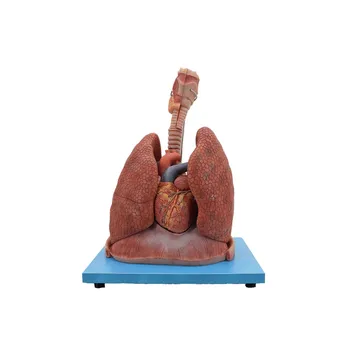

Zhengzhou Meiwo Science & Technology Co., Ltd established in 2009, is a comprehensive technology enterprise for medical education integrating R&D, production and sales. Meiwo Science has independent specimen production workshops and model production workshops covering an area of 10,000 square meters. Meiwo main products involve plastinated animal specimens, soft silicone anatomy models, high simulation soft anatomy models, human & animal anatomy softwares, 3D digital human specimen, biological microscope slides, animal skeletons, etc.